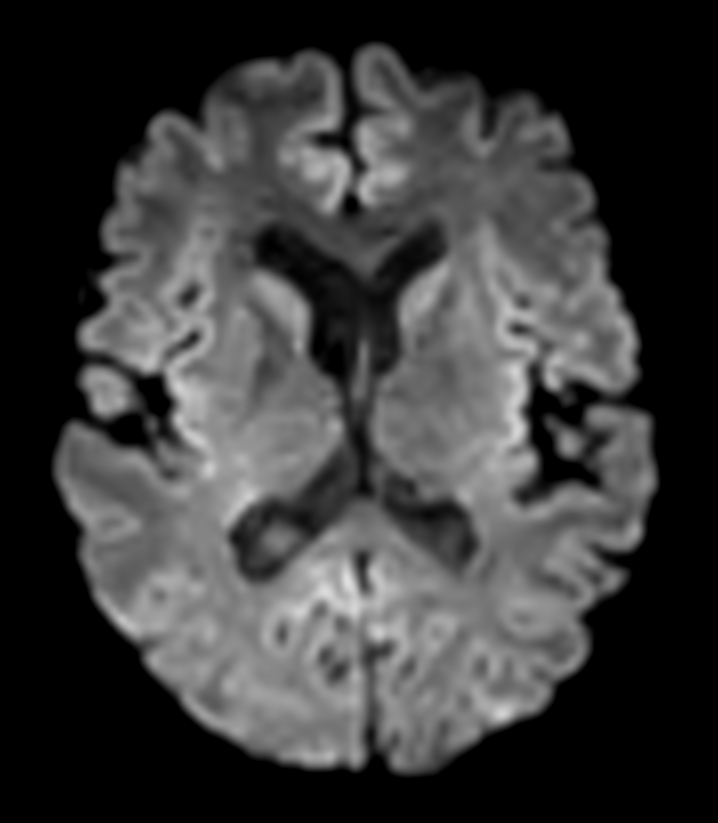

DWI b1000